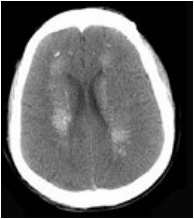

[单选题]男,52岁,无明显不适,CT检查,最可能的诊断为()A.脑血管畸形B.结节性硬化C.甲状旁腺功能低下D.脑颜面血管瘤病E.转移瘤